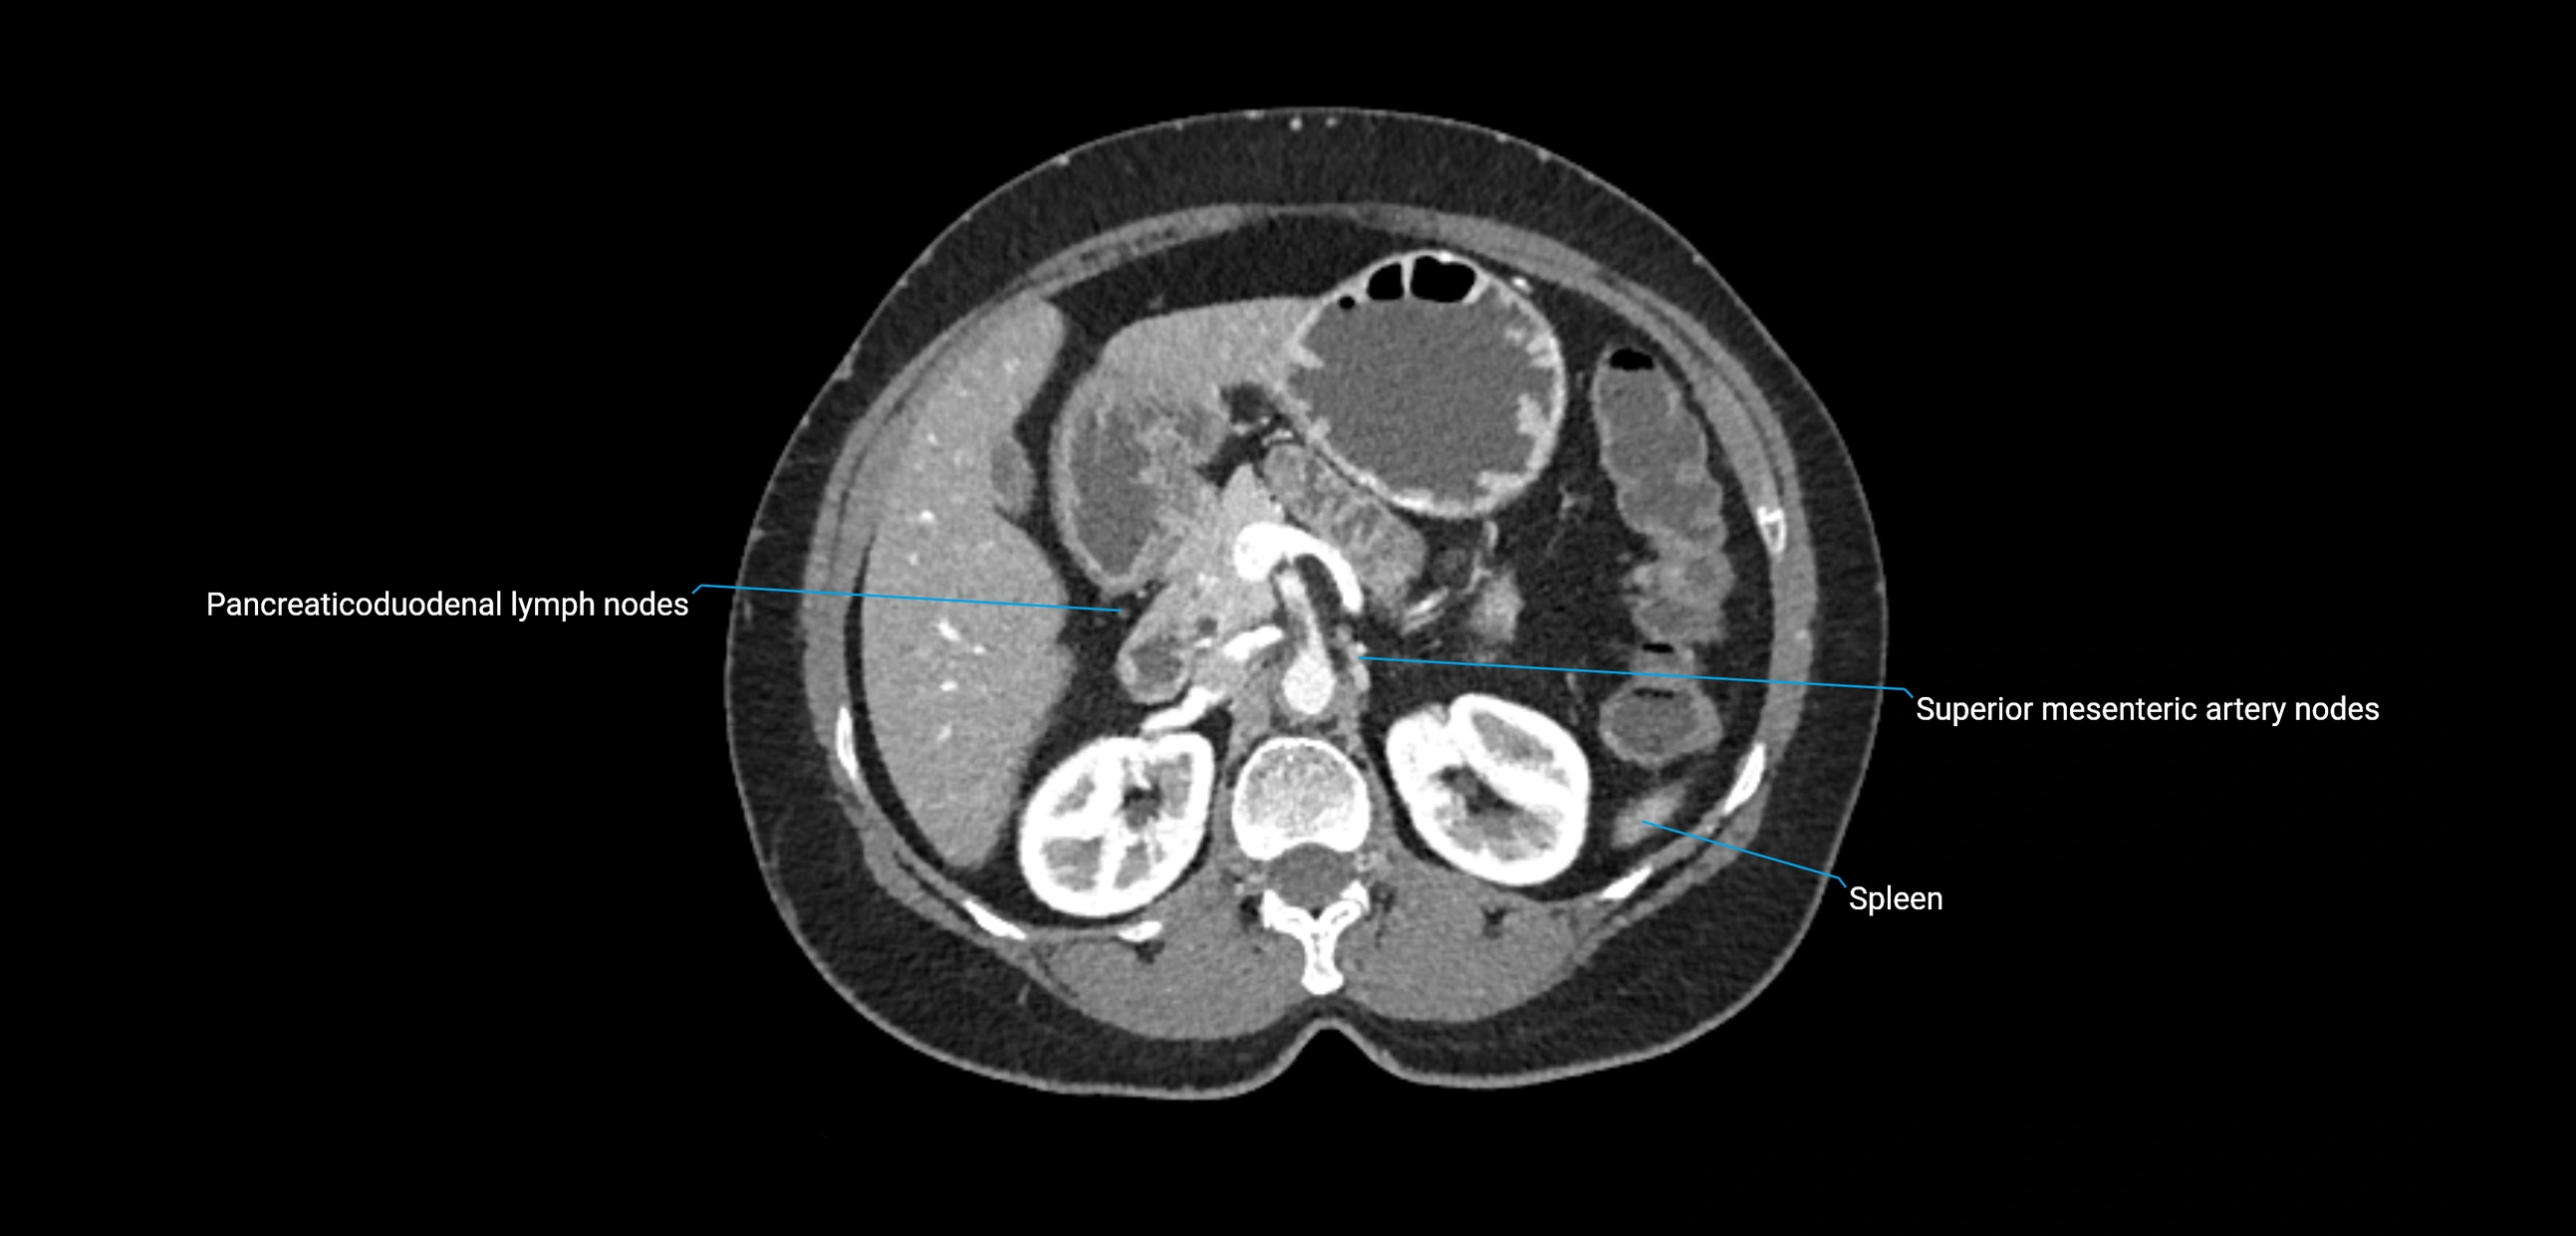

The lateral aortic lymph nodes (also called para-aortic lymph nodes) are a major group of retroperitoneal lymph nodes located along the abdominal aorta and its branches. They lie between the diaphragmatic crura superiorly and the bifurcation of the aorta at L4 inferiorly.

These nodes receive lymph from a wide range of abdominal and pelvic structures. Specifically, they drain lymph from the kidneys, suprarenal glands, gonads (testes/ovaries), uterus, uterine tubes, and pelvic organs, before converging into the lumbar lymphatic trunks, which terminate in the cisterna chyli → thoracic duct.

CT Appearance

CT Pre-Contrast:

• Nodes appear as soft-tissue density nodules adjacent to the aorta and IVC

CT Post-Contrast:

• Normal nodes enhance homogeneously

• Malignant nodes may show heterogeneous enhancement, central necrosis, or conglomerate formation

• Size >1 cm short axis is suspicious, though morphology and distribution are equally important

CT Venography (CTV):

• Demonstrates nodal encasement or compression of adjacent vessels (aorta, IVC, renal veins)

• Useful in staging testicular and ovarian malignancies

• Provides 3D reconstructions for retroperitoneal lymph node dissection planning